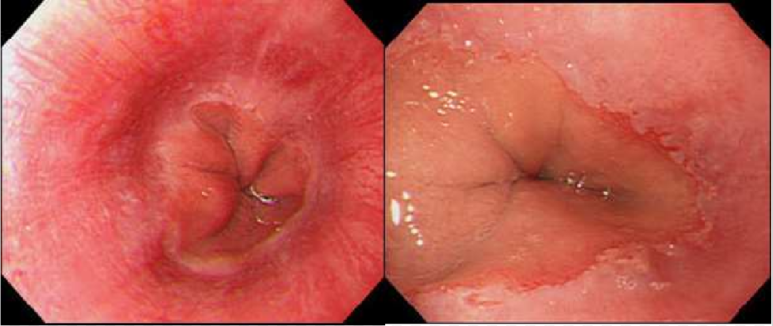

역류성 식도염은 위산이 식도로 역류하여 식도 점막이 손상되면서 염증이 나타나는 질환을 말합니다. 여성환자가 남자환자 보다 많아 성별로 보면 2010년 기준 여성이 6,850명으로 남성 4,870명 보다 많은 것으로 나타났습니다. 여성이 남성보다 역류성식도염에 많이 걸리는 이유는 자극적이고 기름진 식품, 야식 등 불규칙한 식생활 습관과 다이어트 목적의 무리한 체중감량이 원인일 수 있습니다.

정상적인 경우, 위식도 경계 부위가 닫혀 있으나 조절 기능의 약화로 경계 부위가 닫히지 않았기 때문인데 이와 같은 현상이 지속 될 경우 만성적인 역류가 발생해 식도염이 발생하는 것입니다.